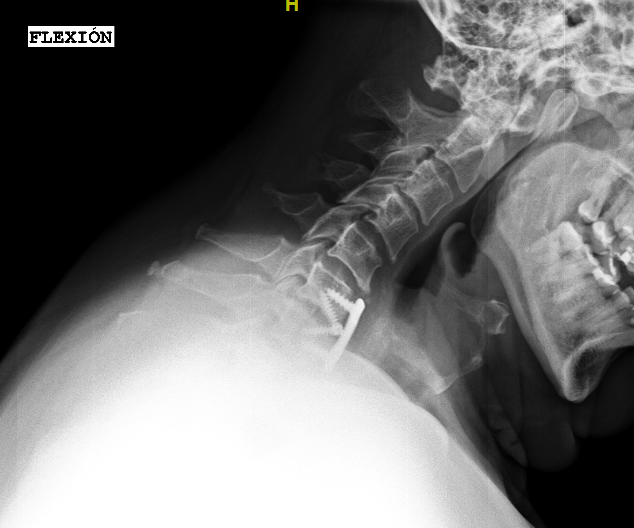

Las RX dinámicas reflejan la ausencia de fusión C6-C7